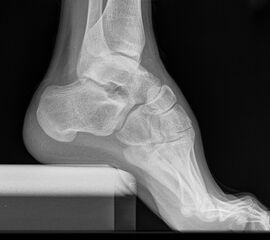

Fersenbein lateral

Positionierung:

• Patient in Seitenlage.

• Fuß mit der Außenseite aufliegend.

• Ferse liegt parallel zum Tisch.

• Röntgenröhre 90° zur Senkrechten.

• Zentralstrahl von lateral nach medial, zentriert auf das Fersenbein ca. 1-2 Querfinger distal der Malleolen.

Kennzeichen des Röntgenbildes:

• Seitliche Darstellung des Fersenbeins mit scharfen Knochenkonturen.

• Gut einsehbares unteres Sprunggelenk (Articulatio talocalcaneonaviculare).

• Gut einsehbares Gelenk zwischen Calcaneus und Os cuboideum.

Besondere Bemerkungen zum Beispielbild:

• Darstellung der Kalkaneus seitlich.

• Kleiner Traktionssporn im Insertionsbereich der Achillessehne.

• Großes Os trigonum dorsal des Talus.